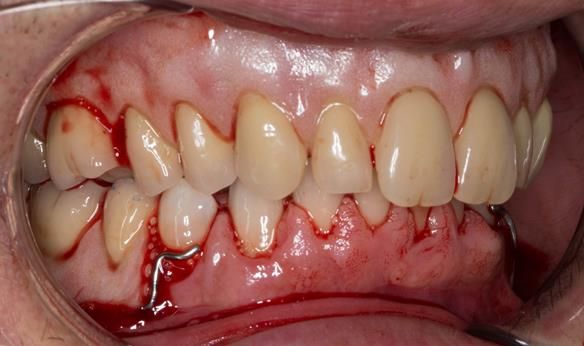

This 52 year old man was referred to me from his general dental practitioner in 2018.

10 years prior to consultation the patient's general dentist diagnosed periodontitis and referred him to Manchester Dental Hospital. He received a treatment plan to manage the periodontitis. Unfortunately, this was not acted on. Four years ago gaps developed between the upper front teeth. Orthodontic treatment was provided to align the teeth. A bonded retainer was fitted onto the upper front teeth. Approximately one year prior to consultation with me the patient noticed the teeth moving again. He consulted his orthodontist, who advised no further orthodontic treatment. One month prior to the consultation with me the upper left central incisor fell out whilst eating.

- Generalised periodontitis; stage IV grade C: currently unstable, risk factors: smoker.

- The remaining maxillary teeth had hopeless prognosis in the short term. They exhibited 80 - 100% alveolar bone loss with increased mobility (Grade 2 - 3).

- The lower right second premolar and lower left first premolar (LR5 LL4) had hopeless prognosis in the short term. They exhibited 80 - 100% alveolar bone loss with grade 3 mobility.

- The remaining mandibular teeth had approximately 30 - 50% alveolar bone loss with grade 1 mobility.

The clinical situation and treatment process is shown in detail below with photographs.